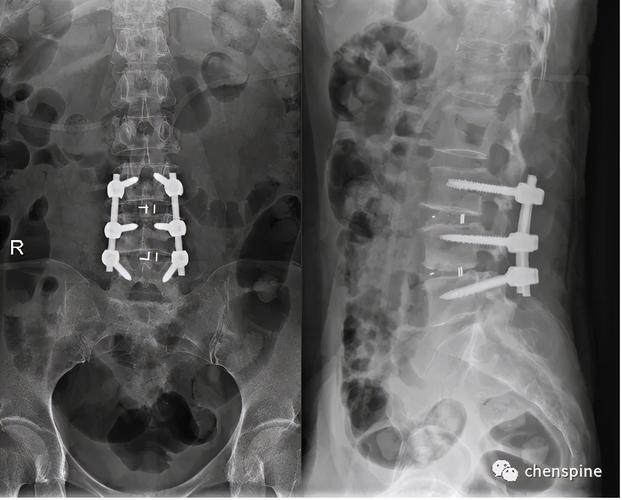

腰椎x线片: 腰椎术后,l3/4-l4/5行腰椎减压植骨融合内固定术